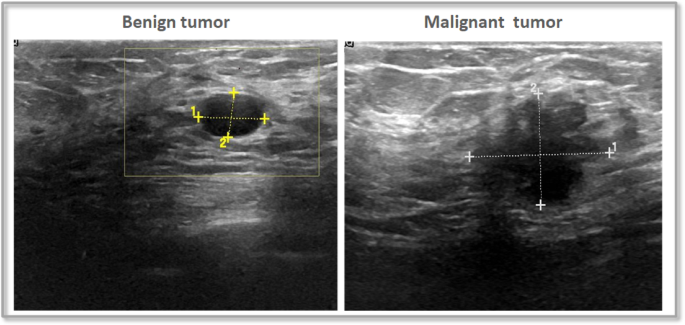

The dataset contains breast ultrasound images gathered from 600 women aged 25 to 75. These images were collected in 2018 and organized into a dataset containing 780 images, each with an average size of 500 × 500 pixels in PNG format. Alongside the original images, there are corresponding ground truth images that categorize each image into one of three classes: normal, benign, or malignant. Figure 5, Illustrates a sample for the applied dataset.

The BUSI dataset has proven to be highly valuable for the development and evaluation of CAD systems, which leverage ML and DL techniques to assist experts in interpreting medical images. This dataset serves as an excellent resource for researchers focused on detecting and diagnosing BC, as well as for healthcare professionals. By utilizing this dataset to train and evaluate ML models, researchers can create CAD systems that improve both accuracy and efficiency in diagnosis. The images within the dataset are categorized into benign and malignant groups based on biopsy results, facilitating precise analysis.

Samples of BUSI dataset.